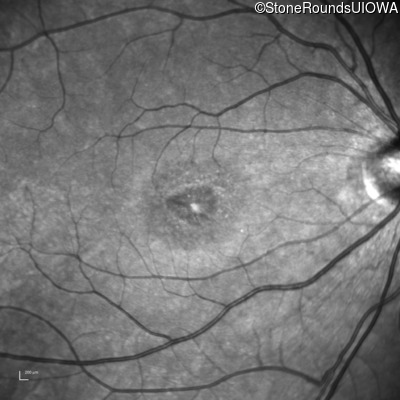

AR Stargardt Disease (IIA)

Age at visit:

15 years

OD

OS

20/125 -1

20/80

AR Stargardt Disease

ABCA4

Val256Val GTG>GTT

Gly1961Glu GGA>GAA

AR